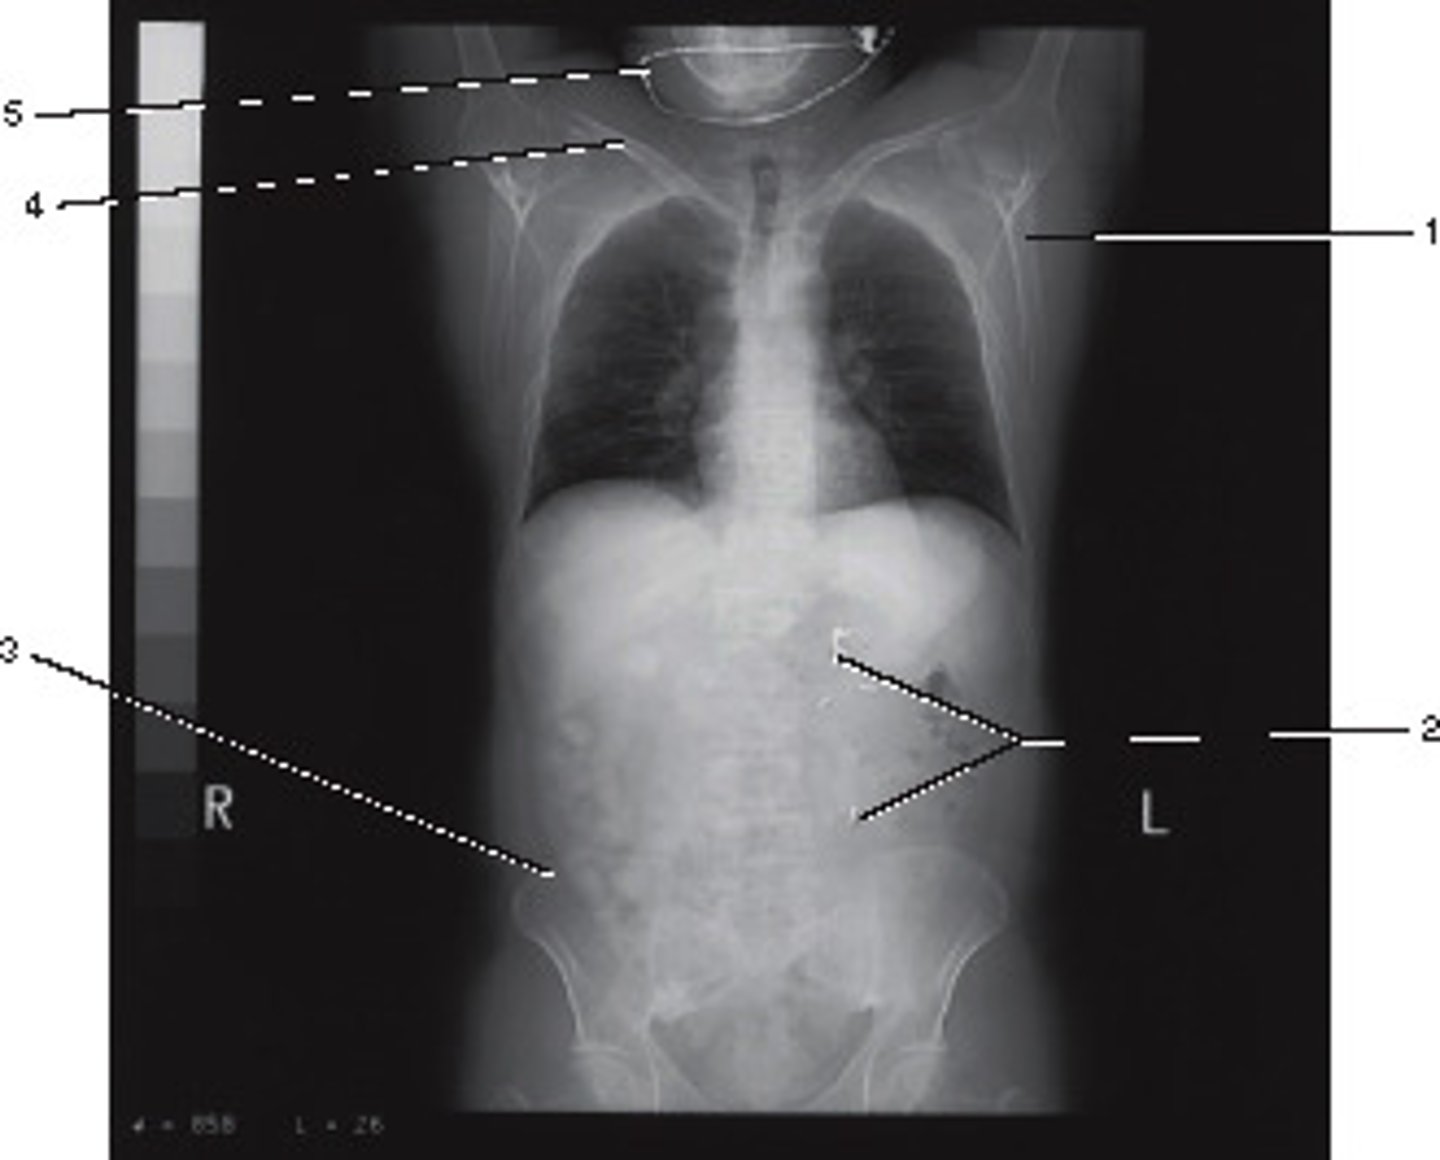

0 degrees;

The Azimuth setting refers to the relationship betyween the x-ray tube and detectors during scout of localizer production.

What azimuth setting was used to obtain this image?

<p>What azimuth setting was used to obtain this image?</p>

Supine

What position was this patient in during data acquisition?

<p>What position was this patient in during data acquisition?</p>

Abdomen and Adomen/Pelvis

This localizer (scanogram) could be used to program which of the following examinations?

<p>This localizer (scanogram) could be used to program which of the following examinations?</p>